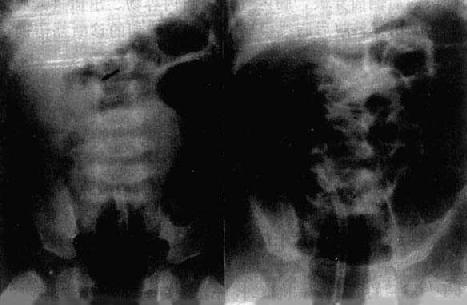

1.单纯性小肠梗阻 梗阻发生后3~6小时可出现X线表现。梗阻近端肠曲胀气扩大。立位像可见肠内高低不等液面,胀气肠曲呈弓形,多发的液面呈梯状排列。早期蠕动亢进,透视可见肠内液面上、下变化活跃。病情发展,肠曲胀气扩大逐渐加重,肠壁张力减低,蠕动明显减弱,液面增宽。肠壁和肠和肠粘膜皱襞除非是慢性梗阻,一般无明显增厚。梗阻远侧肠曲无气或仅见少许气体,因而可根据胀气扩大肠曲所涉及的范围来估计肠梗阻的位置(图4-1-4)。

图4-1-4 小肠梗阻(立位)

中上腹部小肠明显积气、扩张,

有多个液平